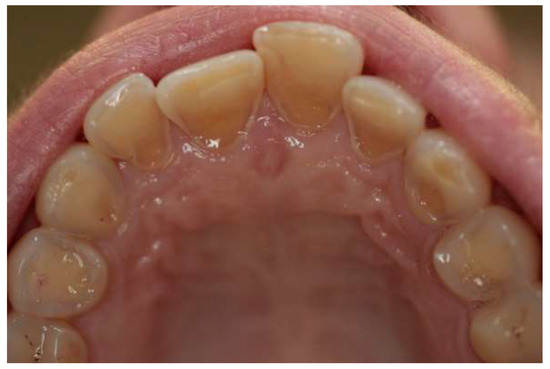

- Grade 0: no erosive changes;

- Grade 1: initial loss of enamel texture;

- Grade 2: visible loss of hard tissues under 50% of the surface; and

- Grade 3: visible loss of hard tissues over 50% of the surface.